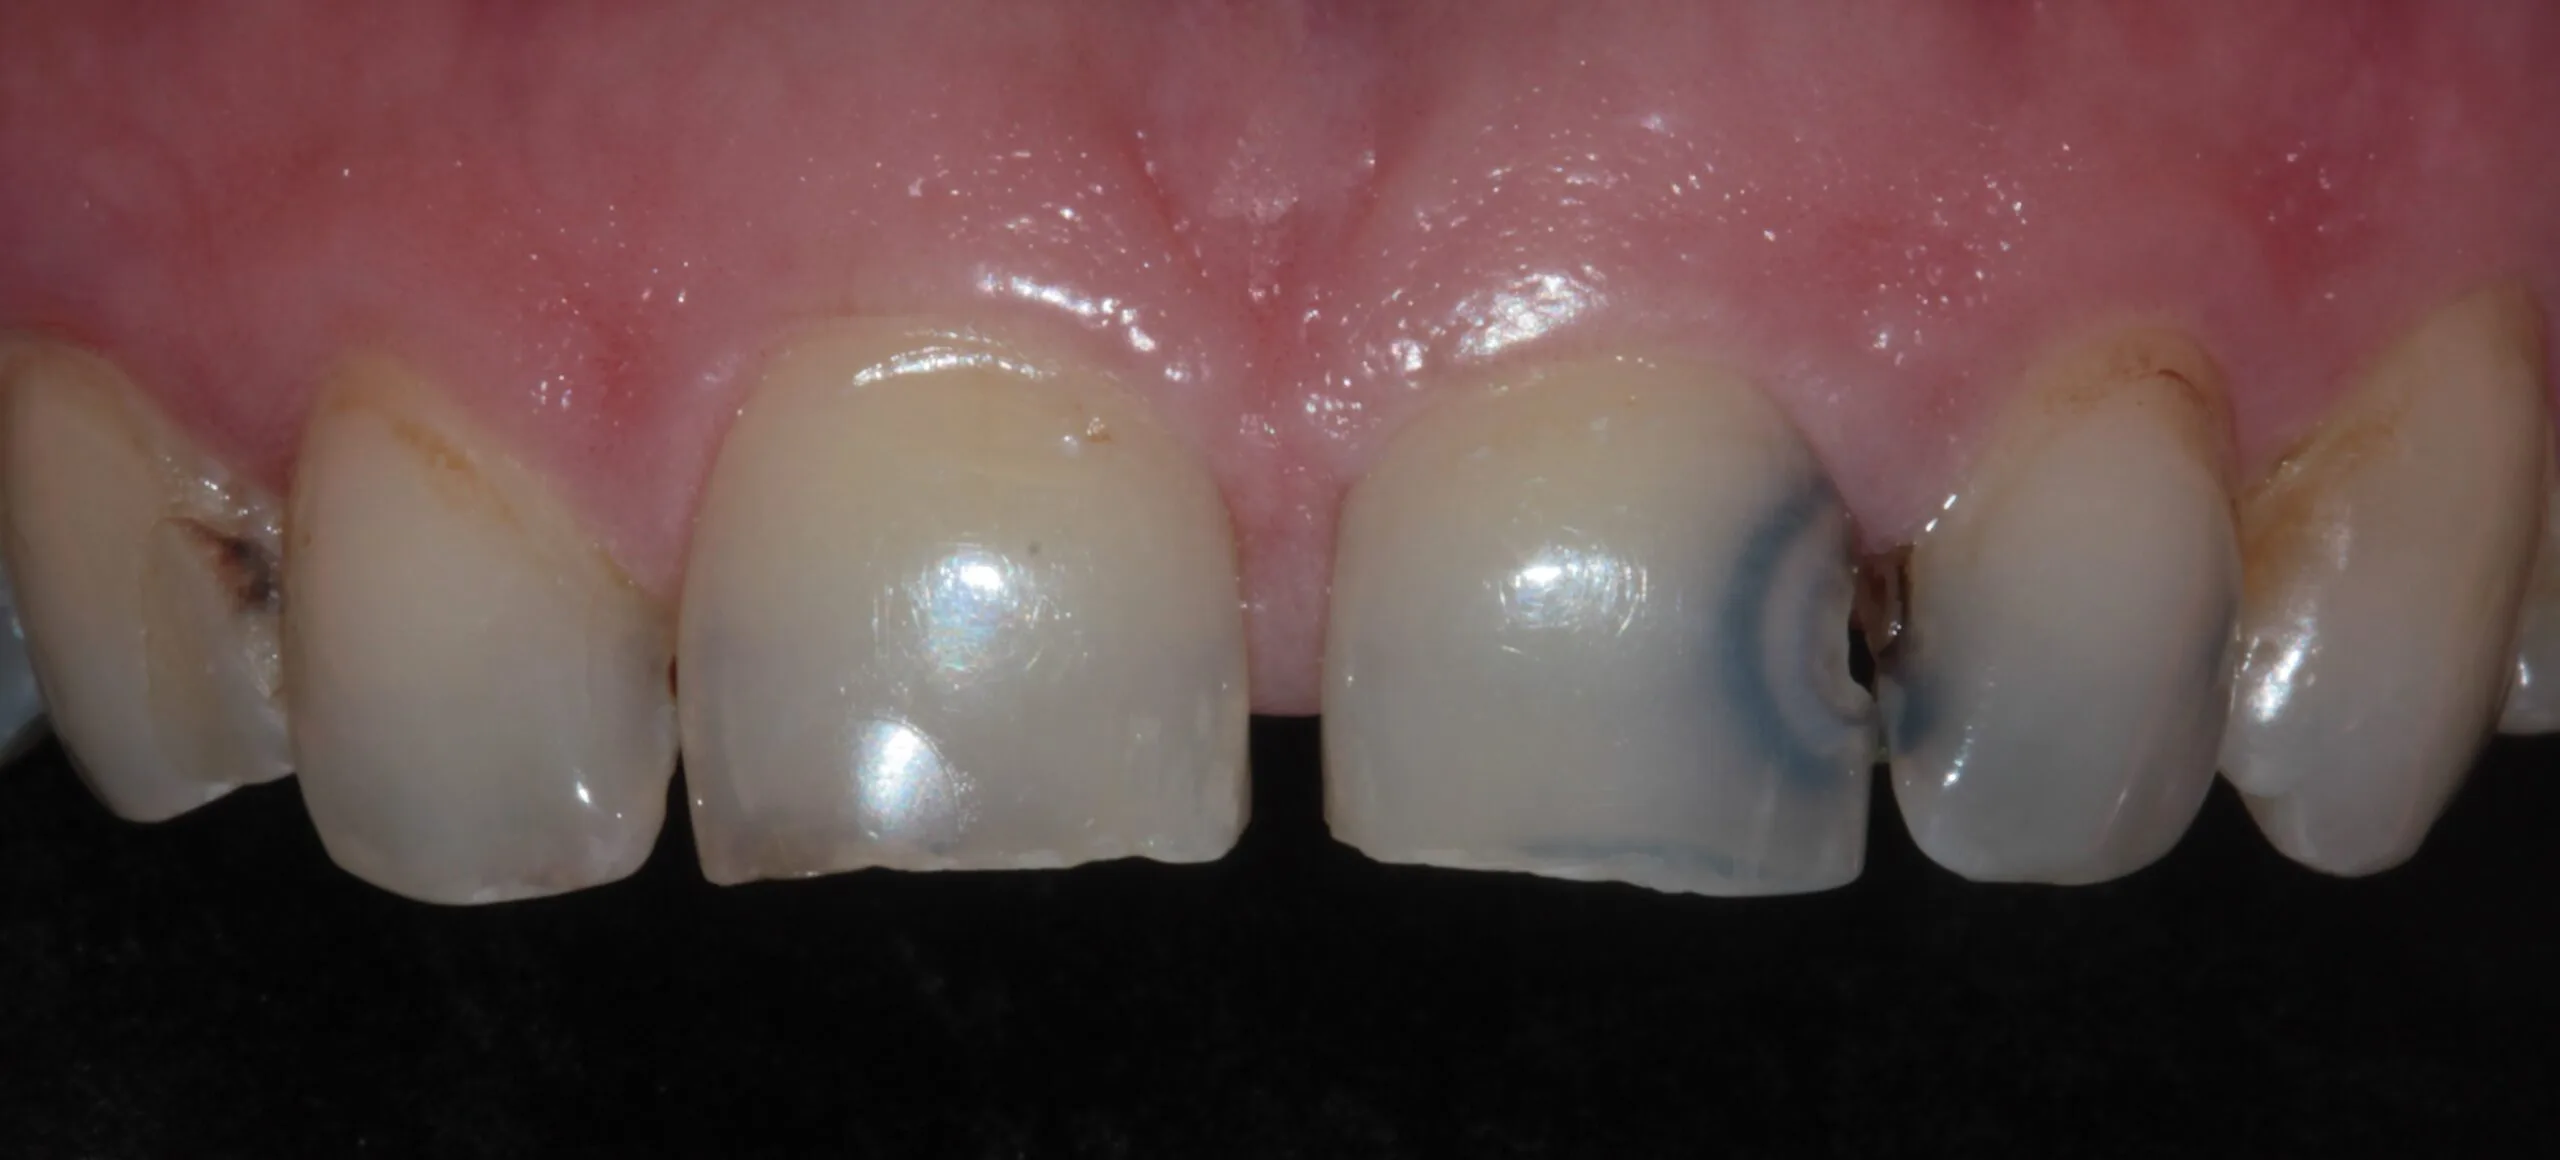

Cosmetic Dentistry